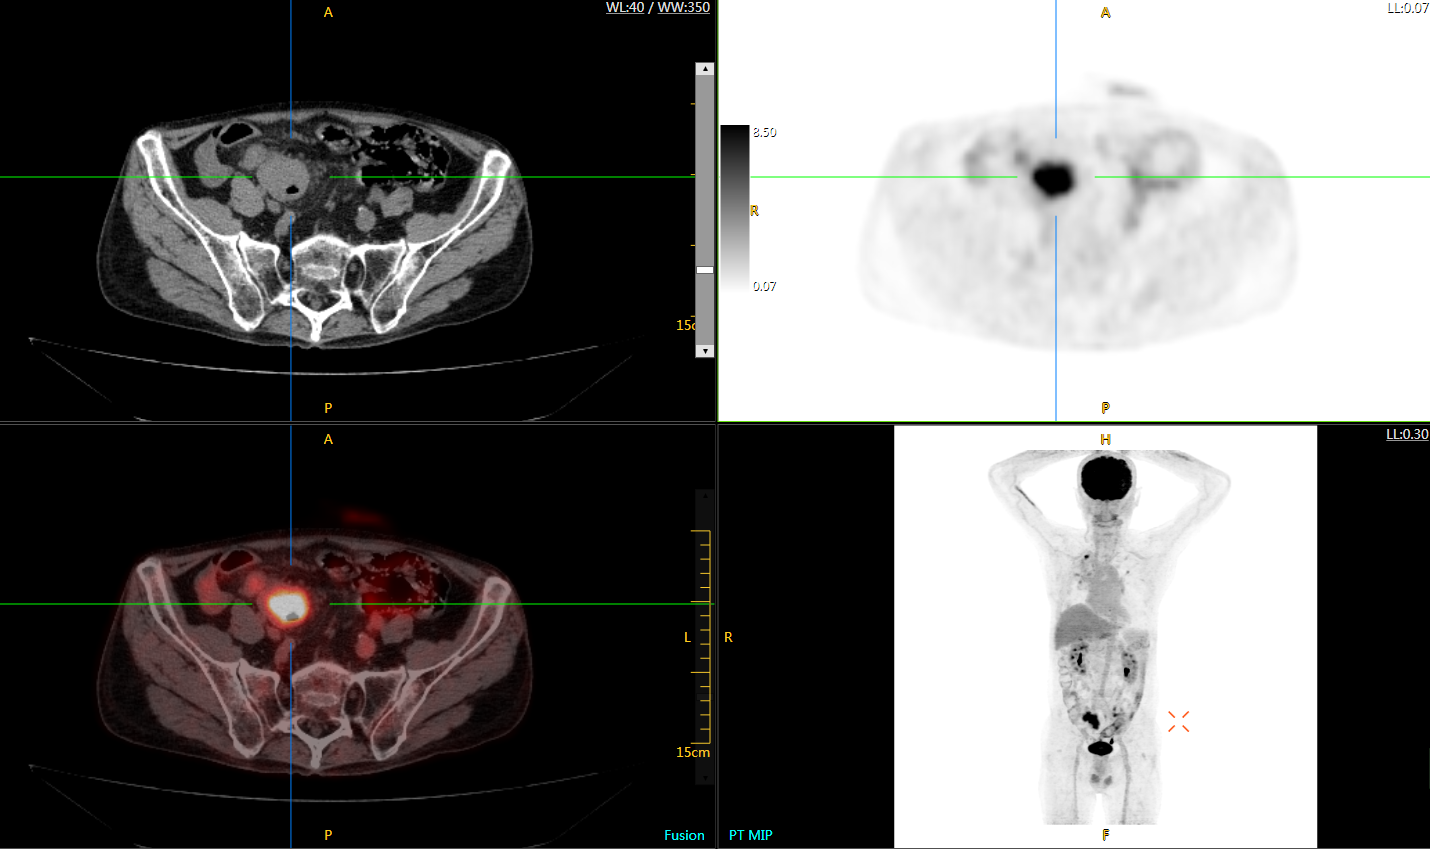

注射總劑量為7.8mCi,注射后1.6小時,基于uEXPLORER探索者掃描1分鐘的圖像

注射總劑量為0.67 mCi FDG(低于常規(guī)劑量的十分之一),基于uEXPLORER探索者掃描15分鐘的圖像

注射總劑量為6.9mCi,注射后10小時,基于uEXPLORER探索者掃描14分鐘的圖像